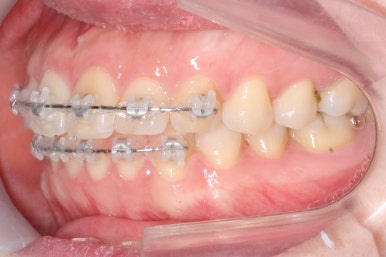

장치를 처음 부착하고 두 번째 조절을 했을 때의 사진입니다.

부분교정의 경우 치료기간을 앞당기기 위해 3주의 내원간격으로 하는 경우가 많은데, 이번의 경우는 결혼식까지 남은 시간이 너무 촉박하여 완벽히 치료를 끝내지 못할 가능성이 컸습니다.

세 번째 조절입니다.

가지런한 정도는 매우 좋아졌고, 군데군데 틈새가 있어서 조여주고 있는 상황입니다.